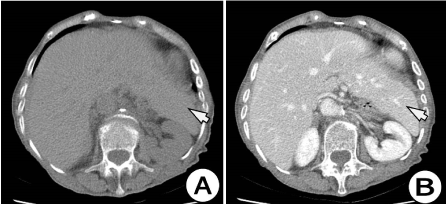

Here in, we present a case of a patient with a pelvic spleen causing discreet abdominal pain or abdominal discomfort. A 67 years old woman was admitted to the surgical department complaining of discreet abdominal pain and lower abdominal tenderness. Physical examination revealed abdominal distention, predominantly in the lower abdomen due to a tender mass. The diagnosis of abdominal wall herniation was suspicions and the patient was undergone to CT investigation of the abdomen. A Computed tomography performed for abdominal wall herniation revealed a pelvic solid formation, well vascularized, approximately 12 cm in length, occupying the pelvis, with a long pedicle of tortuous vessels and with features of an ectopic spleen. (Figures 1 and 2) Axial computed tomography (CT) revealed the absence of the spleen in its normal anatomical position (Figure 3) and a homogeneous pelvic mass with contrast enhancement, suggestive of a ectopic spleen (Figure 4). A contrast-enhanced CT image showed the normal spleen, measuring 12×7 cm, suspended by elongated, dilated, and tortuous splenic vessels (Figures 1,2,5). Imaging findings of the ectopic spleen are the absence of the spleen in its normal position and a mass located anywhere in the abdomen or pelvis with enhancement pattern of a normal splenic tissue (Figure 5). The absence of the spleen in its normal position and the enhancement of the pelvic mass made the diagnosis of an ectopic spleen undeniable. Thorough investigation revealed no evidence of accessory spleens in the left upper quadrant,

Figure 3. Axial native CT (A) and contrast enhanced CT images of the upper abdomen. CT examination of the abdomen showing that here is no splenic tissue at left upper quadrant. Clearly visible hepatomegaly, the left liver lobe is hypertrophic and fills the spleen bed (white arrow)

Figure 4. Axial native (A) and post IV contrast CT scan images of the abdomen: arterial phase (B), venous phase (C) and late phase (D) (arterial phase) showing a ectopic spleen located in left side of pelvis (white arrow), with tortuous vascular pedicle containing the splenic vessels (black arrow)